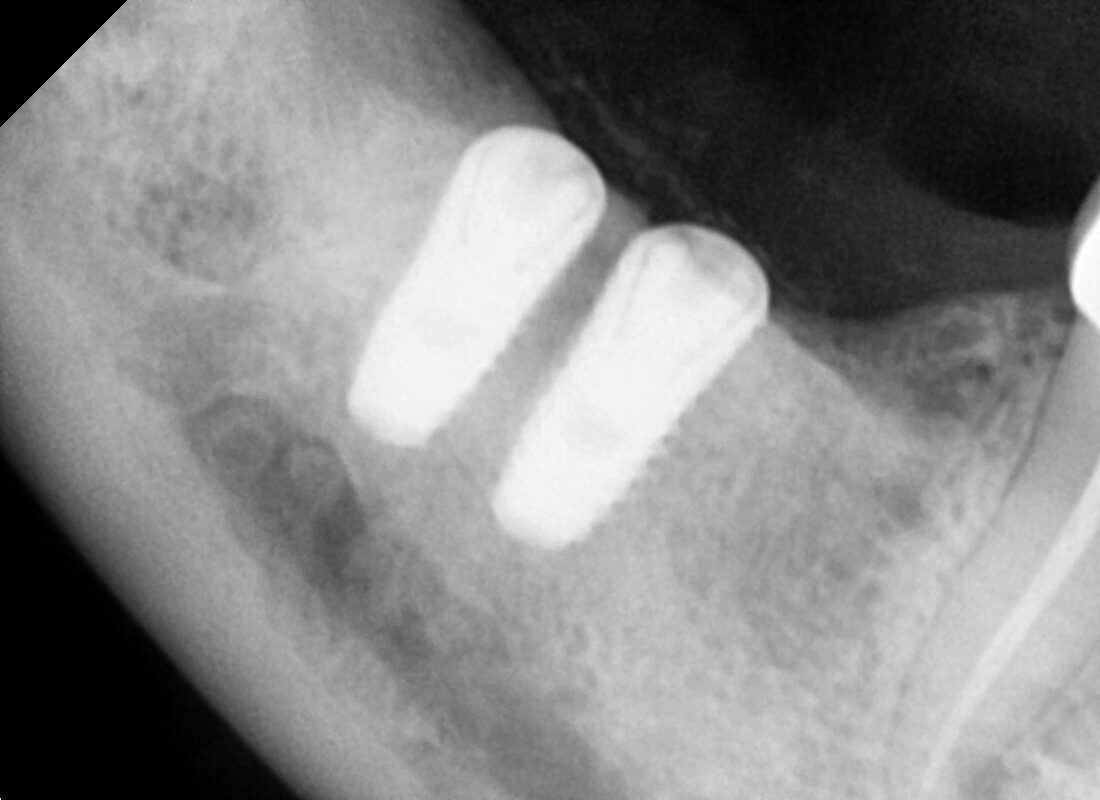

TWO IN MAXILLARY ARCH (INDIRECT SINUS LIFT)